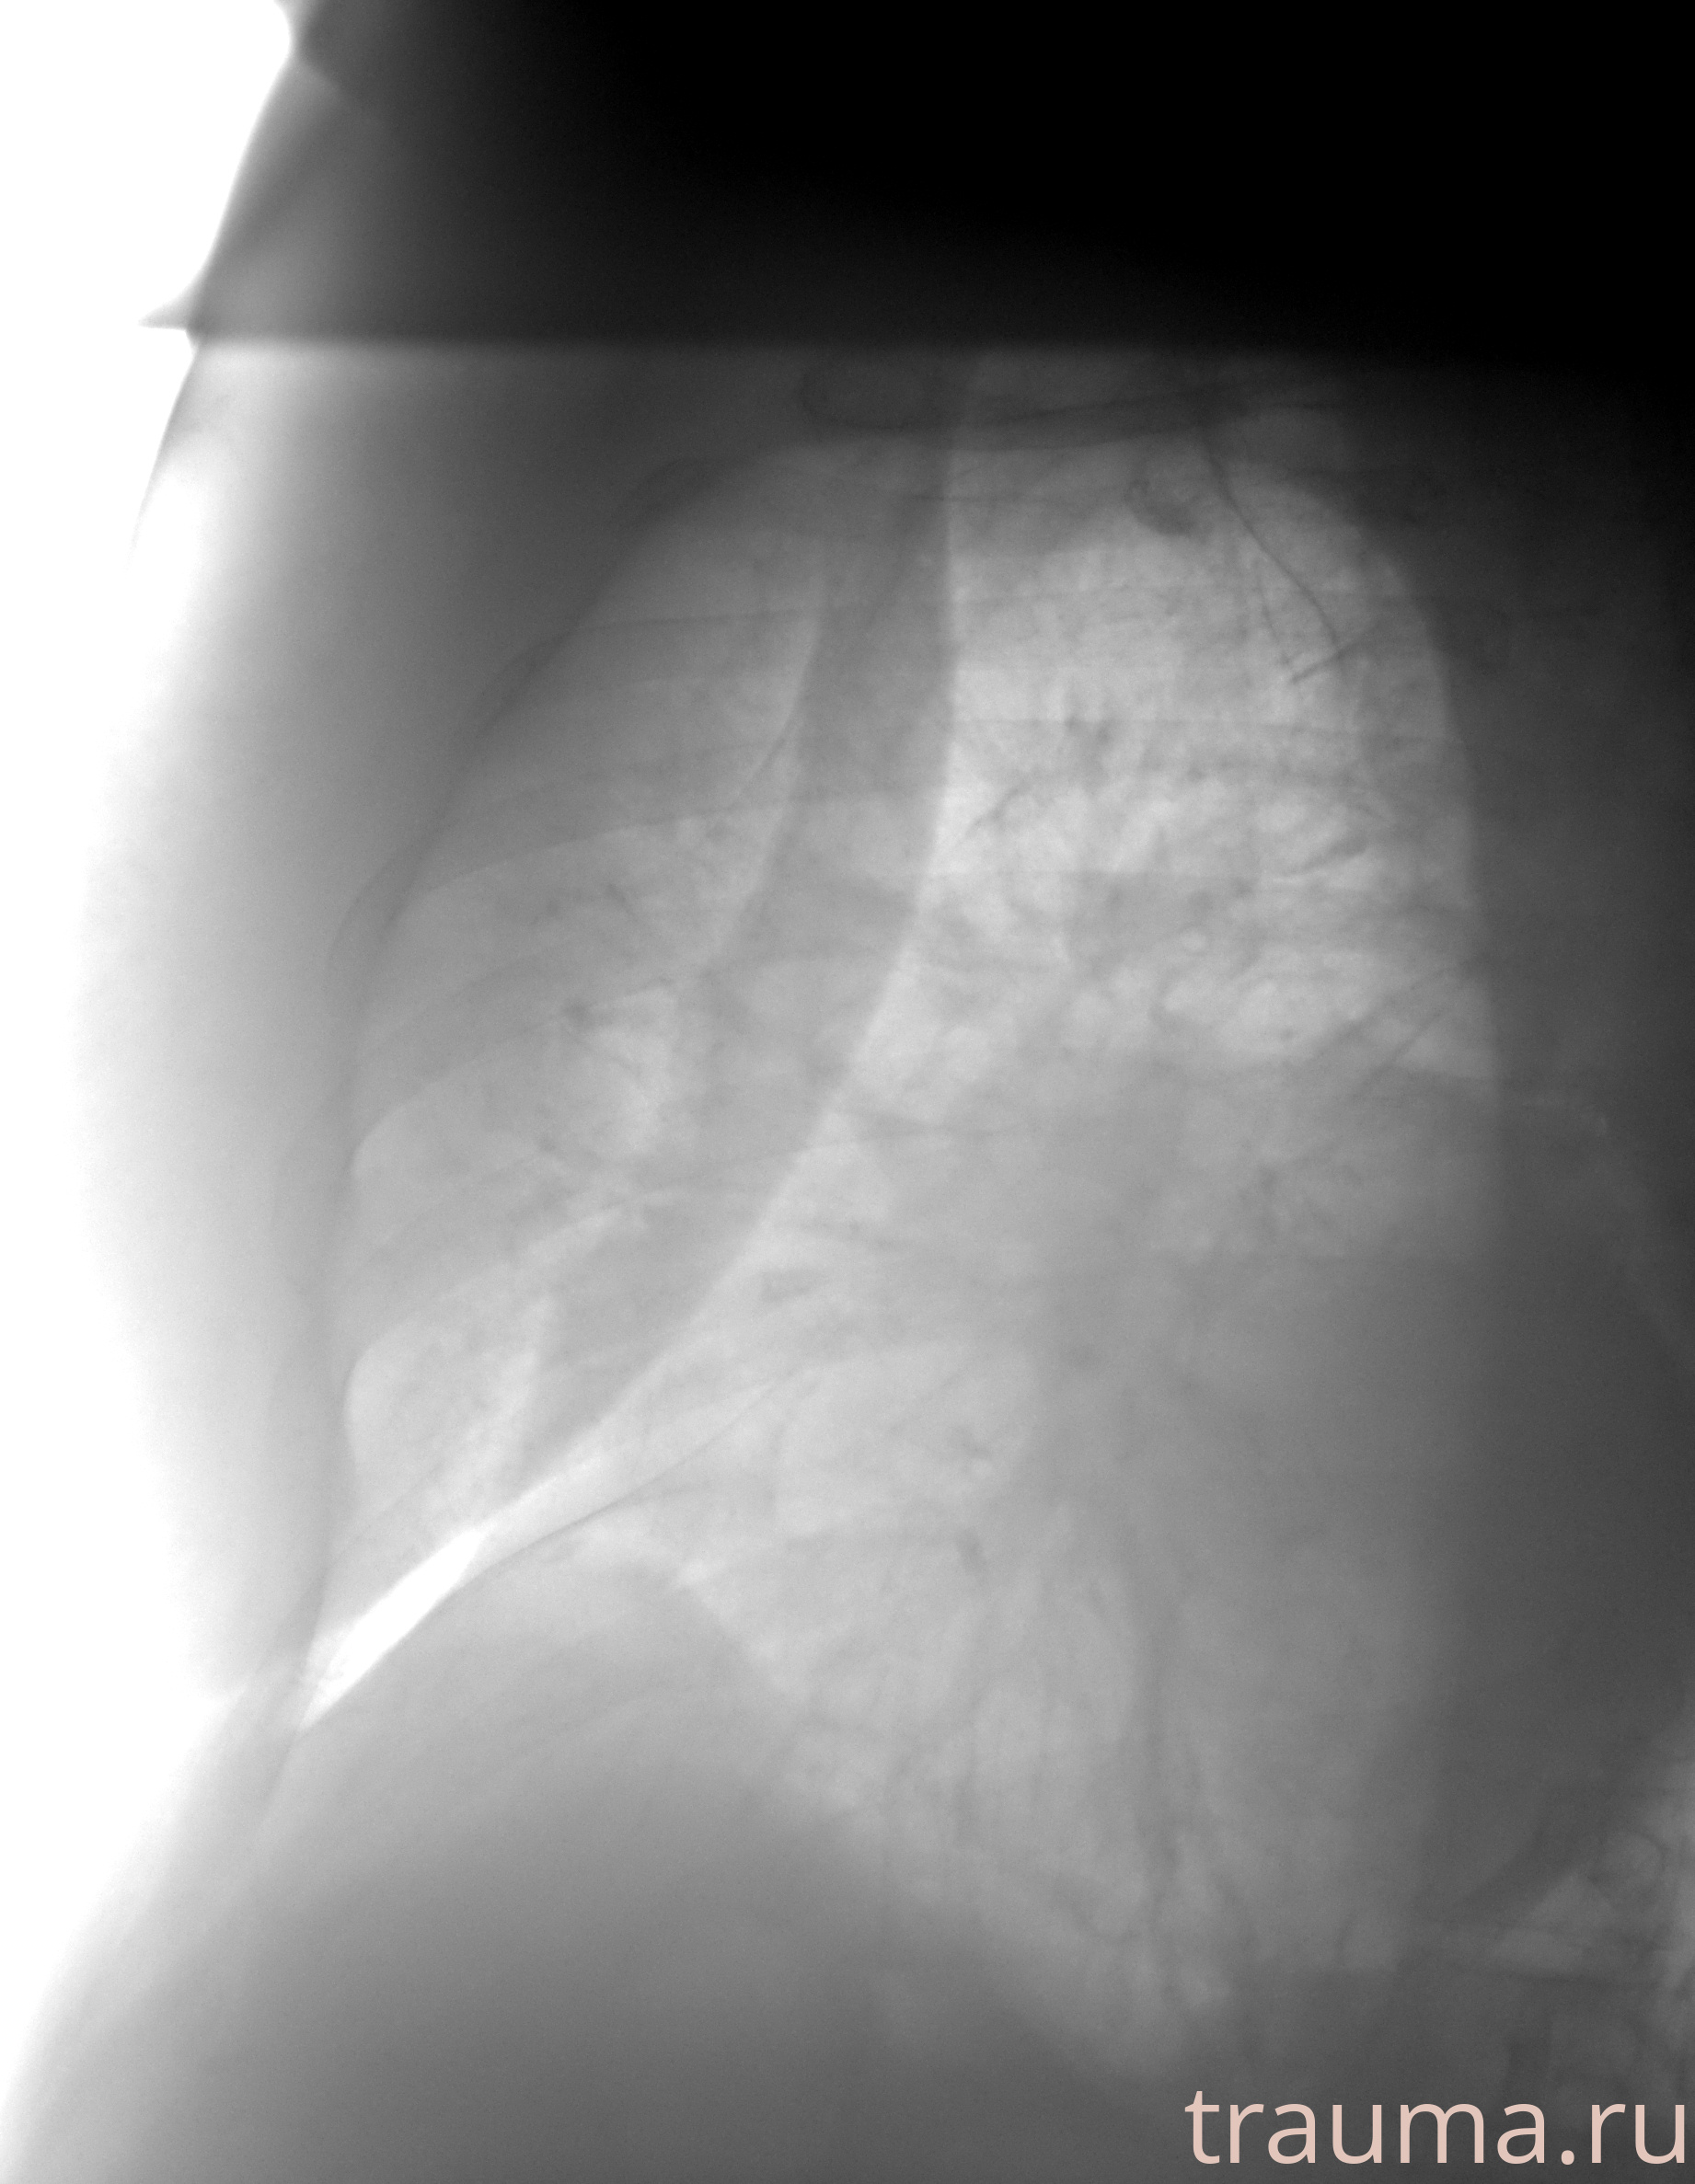

Рентген на дому: по вашему адресу приезжает врач-рентгенолог, травматолог-ортопед с мобильным рентгеновским аппаратом, проводит диагностику травмы или заболевания, делает необходимые рентгенограммы, дает рекомендации по дальнейшему лечению. Получить качественные снимки в домашних условиях возможно благодаря уникальной методике, разработанной МосРентген Центром для института  Склифосовского

при переломе шейки бедра и пневмонии от компании МосРентген Центр - партнера Института имени Склифосовского